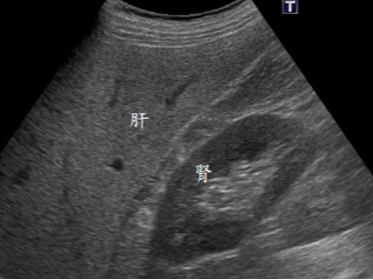

신장(콩팥) 질환

- 신장 결석

- 수신증

- 신장 낭종

- 신세포암